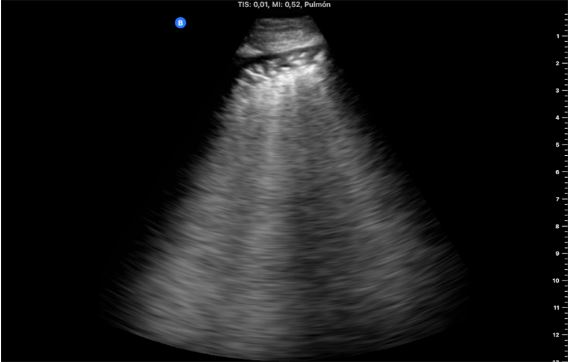

Presentamos tres casos consecutivos de pacientes con cáncer de mama que acudieron a consulta por tos seca persistente, disnea leve o febrícula con antecedente común de tratamiento con radioterapia. Se realizó ecografía pulmonar identificando líneas B focales en campos pulmonares irradiados y engrosamiento e irregularidad pleural, la más llamativa con consolidación, sin derrames.

Ante la duda diagnóstica, en dos casos se inició tratamiento antibiótico empírico y se repitió ecografía a los 7 días, sin cambios clínicos ni ecográficos, apoyando la sospecha de neumonitis rádica no infecciosa. Posteriormente, en las tomografías computerizadas de control oncológico realizadas semanas después, nuestros hallazgos fueron confirmados.